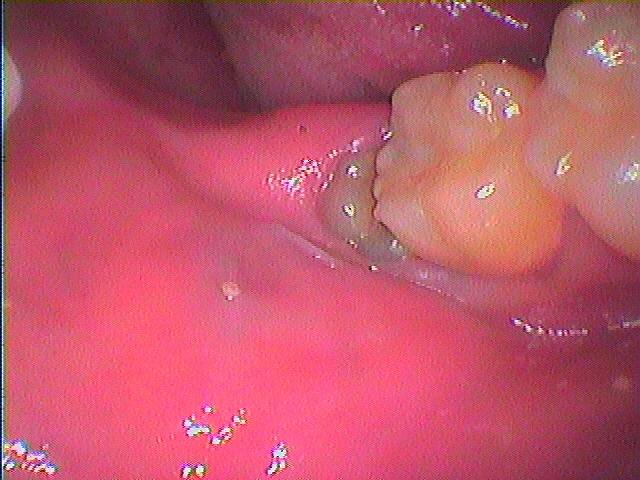

麻酔をかけ歯間部を分割していきます

歯間部がきれいに取れました

麻酔をかけ歯間部を分割していきます

歯間部がきれいに取れました